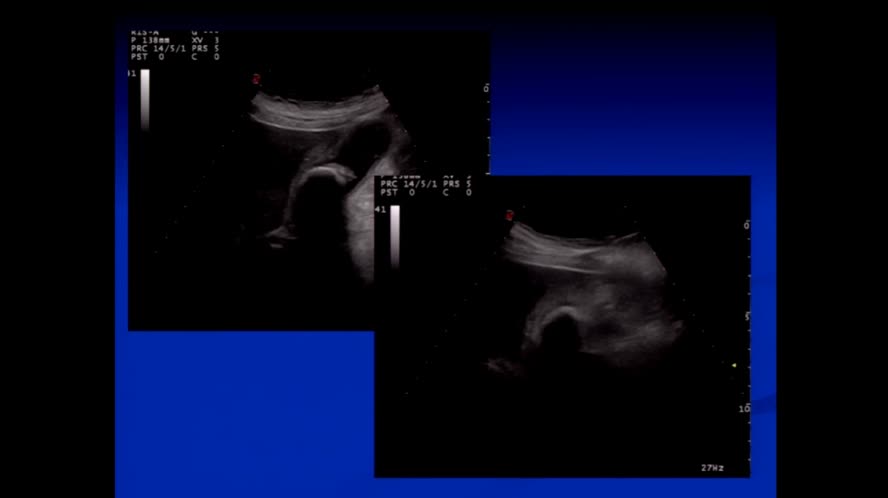

Infezioni pelvi femminile

Congresso

: Ecografia Clinica nelle Malattie Infettive

Autori

: S. Speca |

Data

: 21 marzo, 2016 |

Lingua

: ITA |